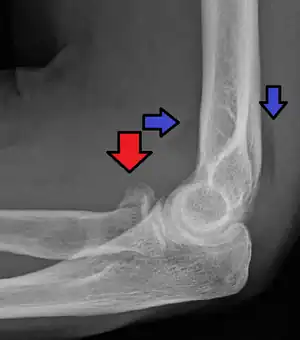

| Radial head fracture (red arrow) with posterior and anterior sail sign (blue arrows) | |

Radial head fractures are diagnosed from an assessment and diagnostic imaging. Assessment may include pain or tenderness at the radial head, bruising, swelling, and a limited range of motion of the elbow.[9] Diagnostic imaging may include ultrasound, plain X-ray, CT scan, and magnetic resonance imaging (MRI).[9][10] A fat pad sign may be present on diagnostic imaging and may indicate a radial head fracture.[11]